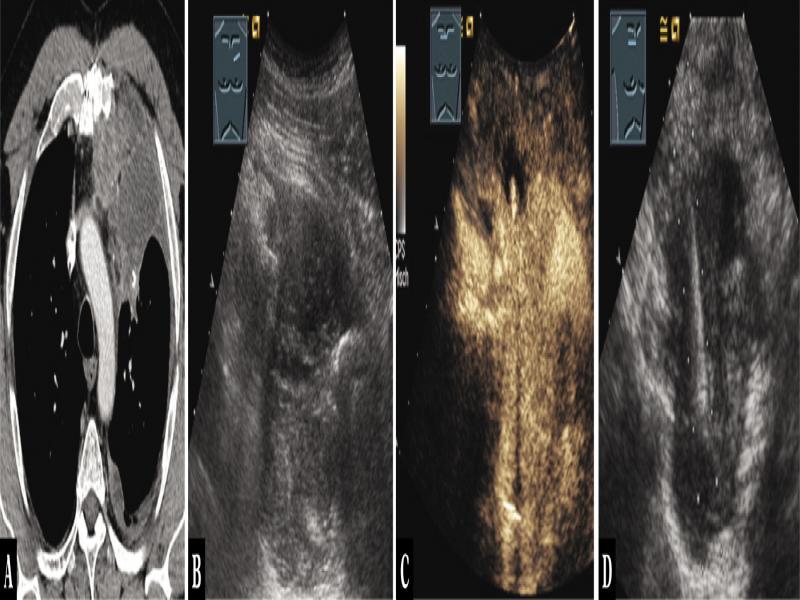

Fig. 7.

A 68-year-old male patient with thoracic pressure sensation and tumor in the anterior mediastinum on computed tomography (A). Thoracic ultrasound indicated an inhomogeneous hypoechoic tumor (B), which showed hyperenhancement on contrast-enhanced ultrasound, as in malignant lymphoma (C). Ultrasound-guided biopsy was performed (D), and the diagnosis of diffuse large B-cell lymphoma was histologically confirmed